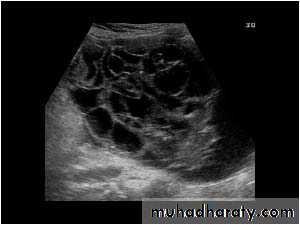

POLYCYSTIC OVARY SYNDROME

Images from women with differing expressions of the four major subtypes of the metabolic syndrome associated with polycystic ovary syndrome (A–D). The images exhibit quite differing ultrasonographic appearances in the size and distribution of follicles within PCOS ovaries. A recent corpus luteum is clearly visible in the ovary in panel (D).

• POLYCYSTIC OVARY SYNDROME